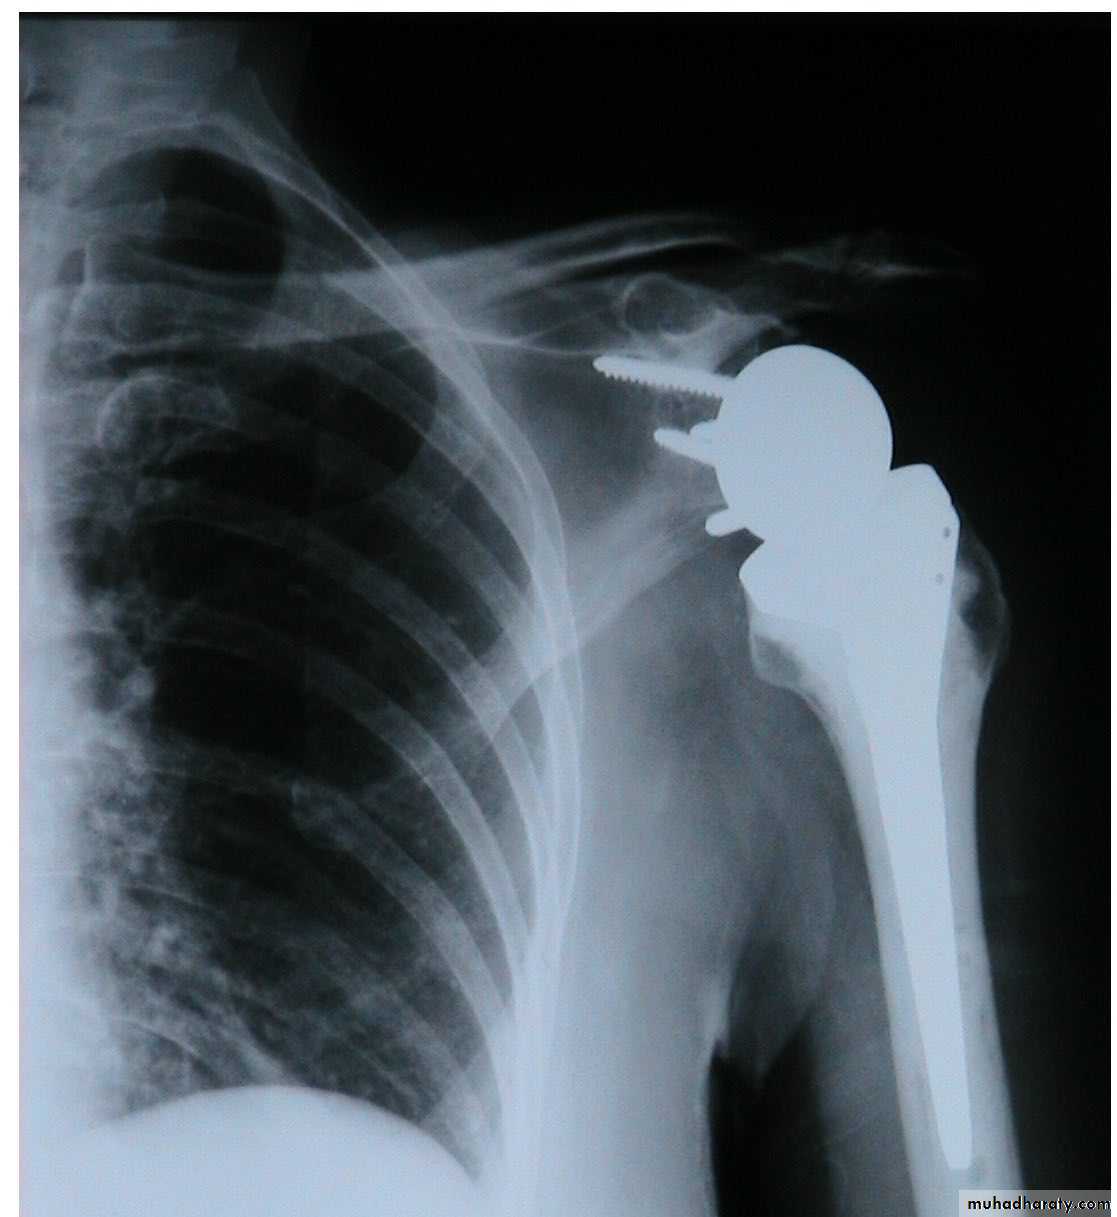

ARTHROPLASTY

36